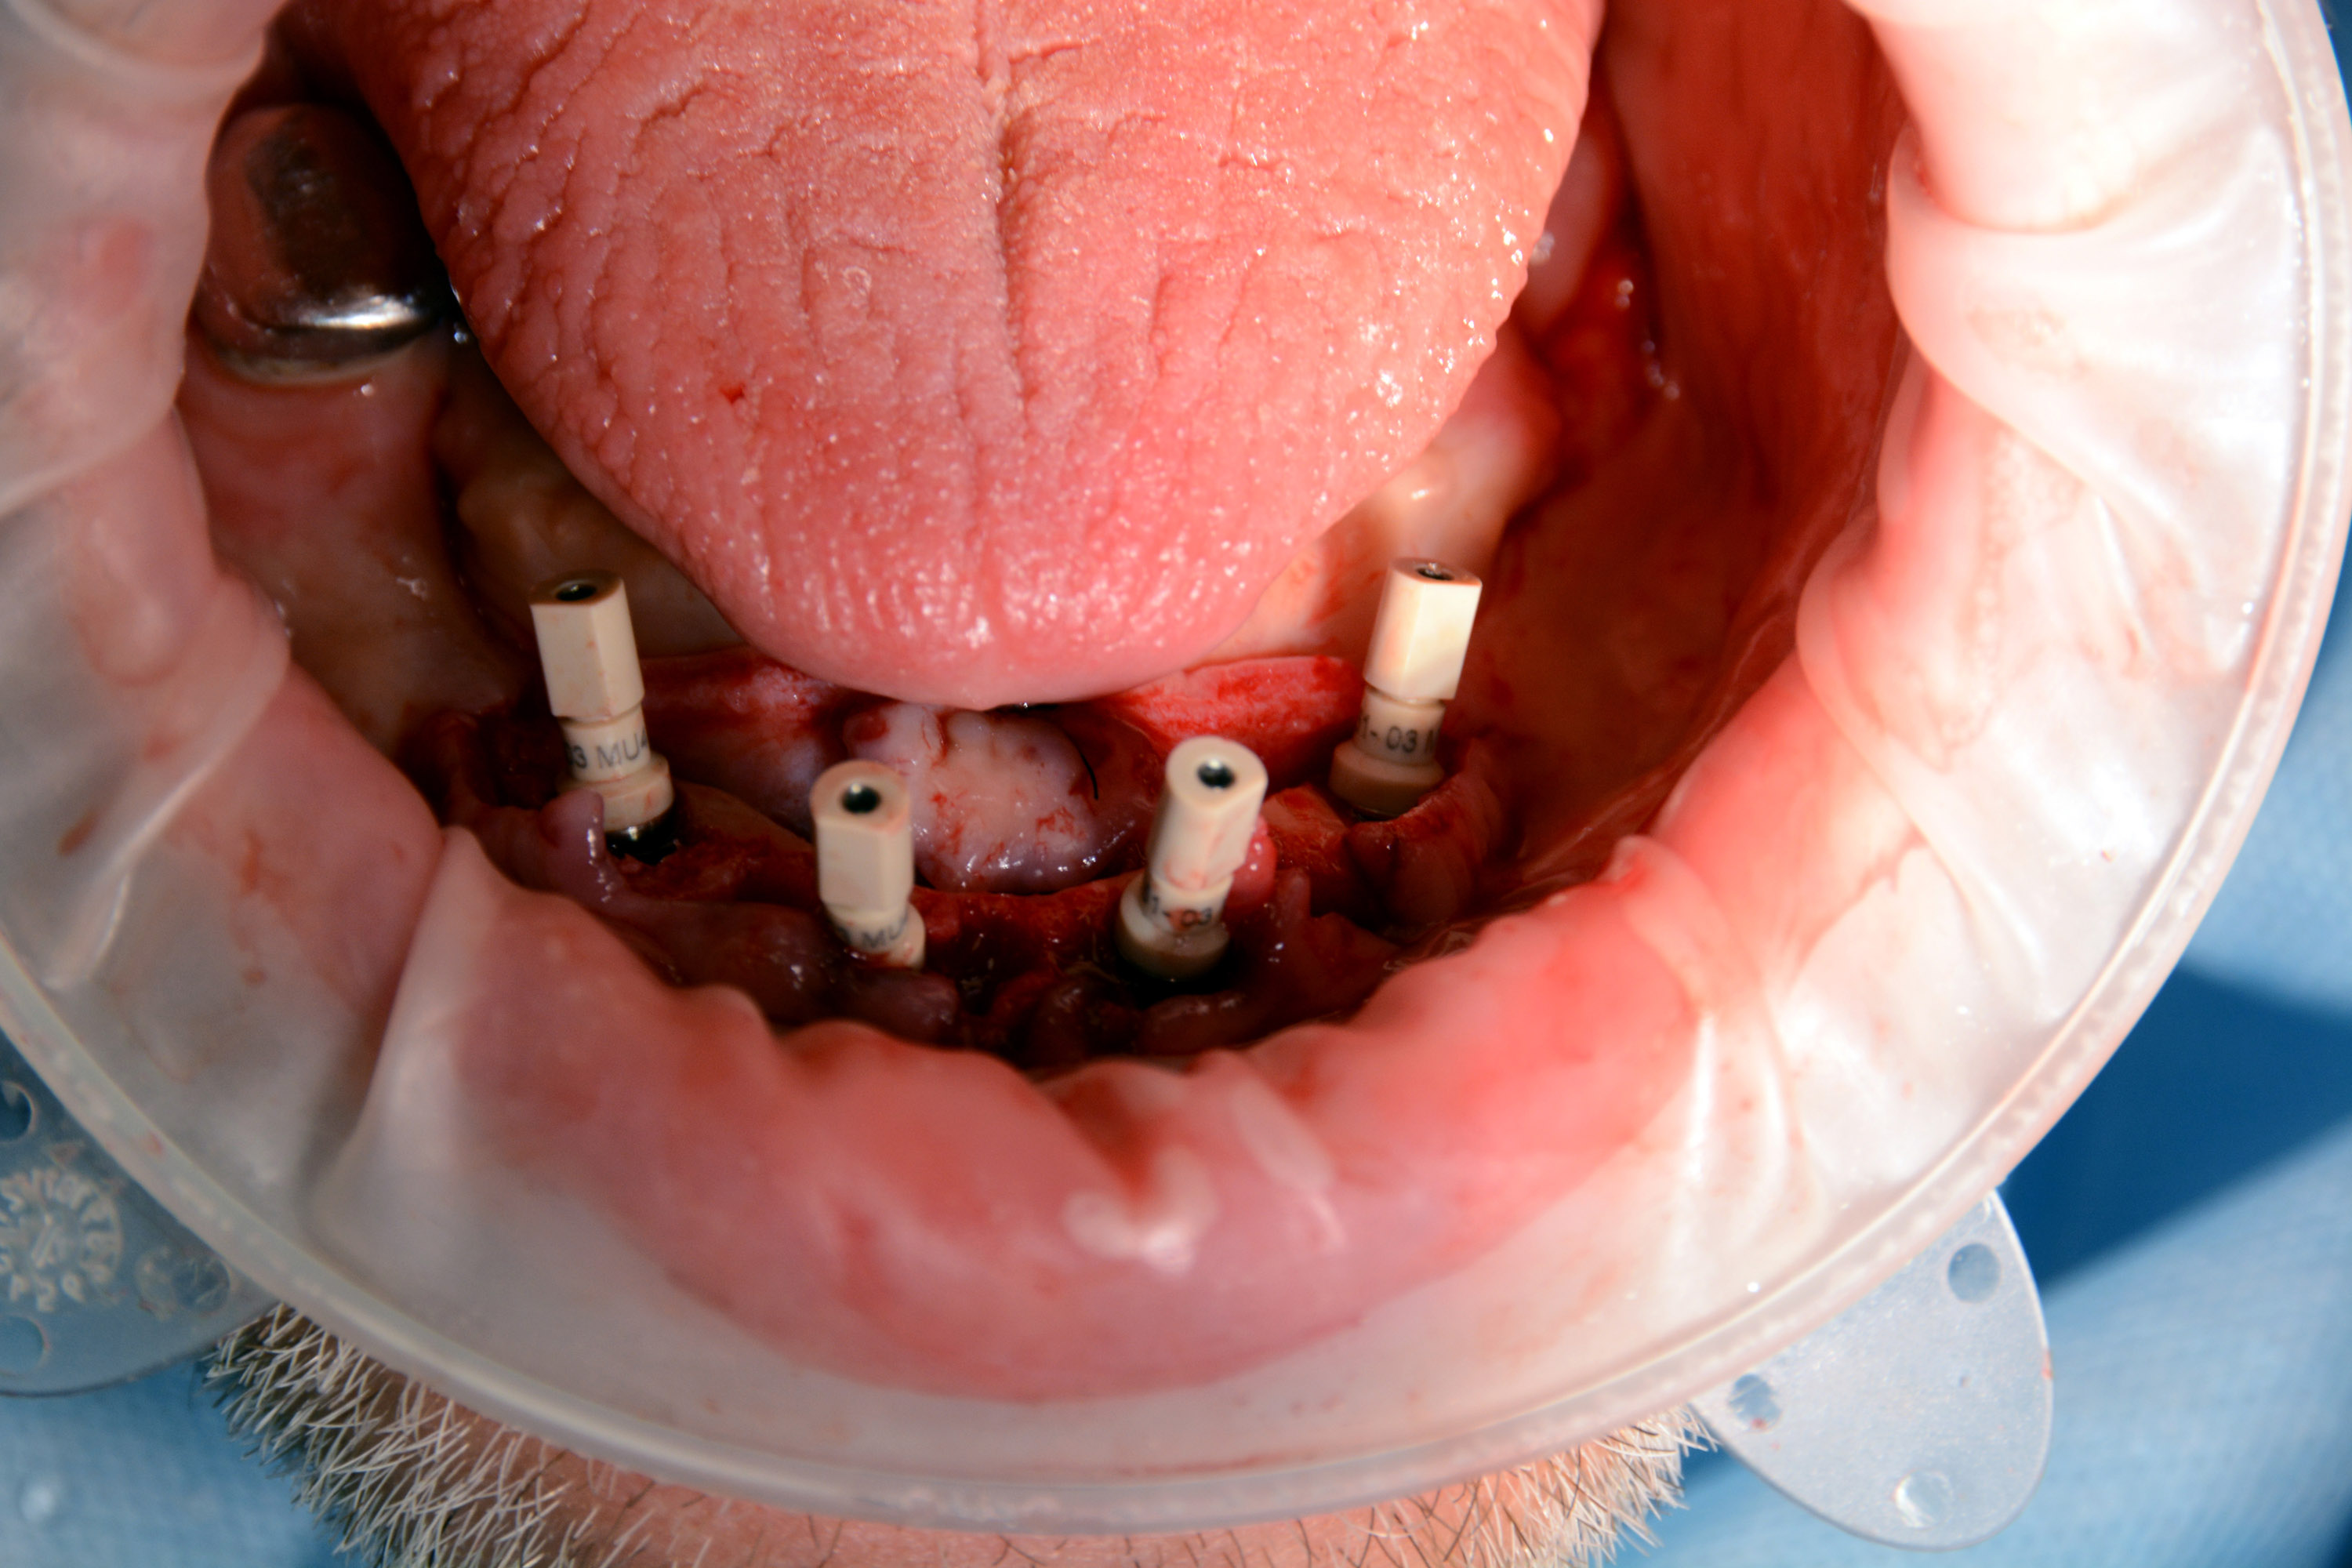

Następnie kursanci pod kierunkiem Dyrektora Naukowego Instytutu Vivadental Dr n. med. Violetty Szycik oraz Mentora Sesji Dr n. med. Adama Nowickiego czynnie uczestniczyli w dwóch złożonych zabiegach z wykorzystaniem pełnej nawigacji chirurgicznej.

Pierwszy zabieg polegał na usunięciu 6 zębów w żuchwie i wprowadzeniu 4 implantów z wykorzystaniem szablonu chirurgicznego do pełnej nawigacji. Bezpośrednio po zabiegu zostały przykręcone multiunity do implantów i osadzony tymczasowy most.